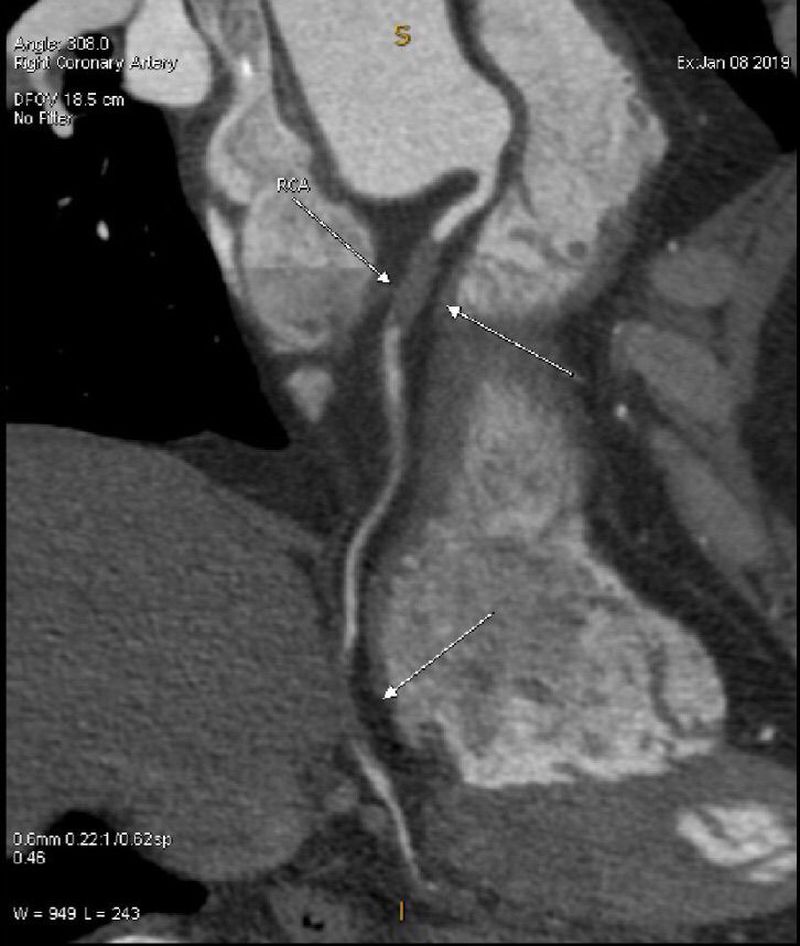

This is the angiogram which was done on the day of heart attach!!! Which says 100% block in the RCA but how come the flow of blood comes way down ?! đ¤ please give me your valuable comments ...

Looks like a Cardiac CT. If you have 10mm MIP and/or VRT for that scan, it would help a lot.